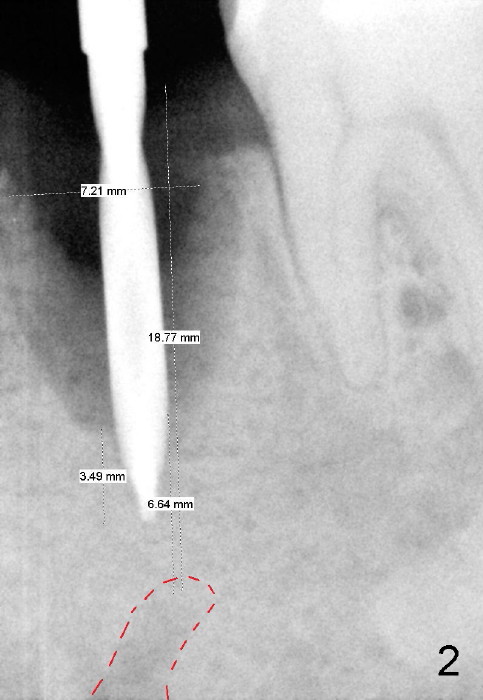

A 54-year-old lady has poor dentition.  She seeks treatment because of pain associated with tooth fracture in the lower left 2nd premolar (Fig.1 arrow).  The best option seems to be extraction and immediate implant.  Thorough curettage after extraction is a key to get rid of infection.

To avoid injury to the mental loop (Fig.2 dashed line), the depth of initial osteotomy is tightly controlled apical to the bottom of the socke.  Accurate measuring is the 2nd important measure to assure no or minimal neurological trauma. The wide socket (due to infection) allows to place an implant as wide as 7 mm.